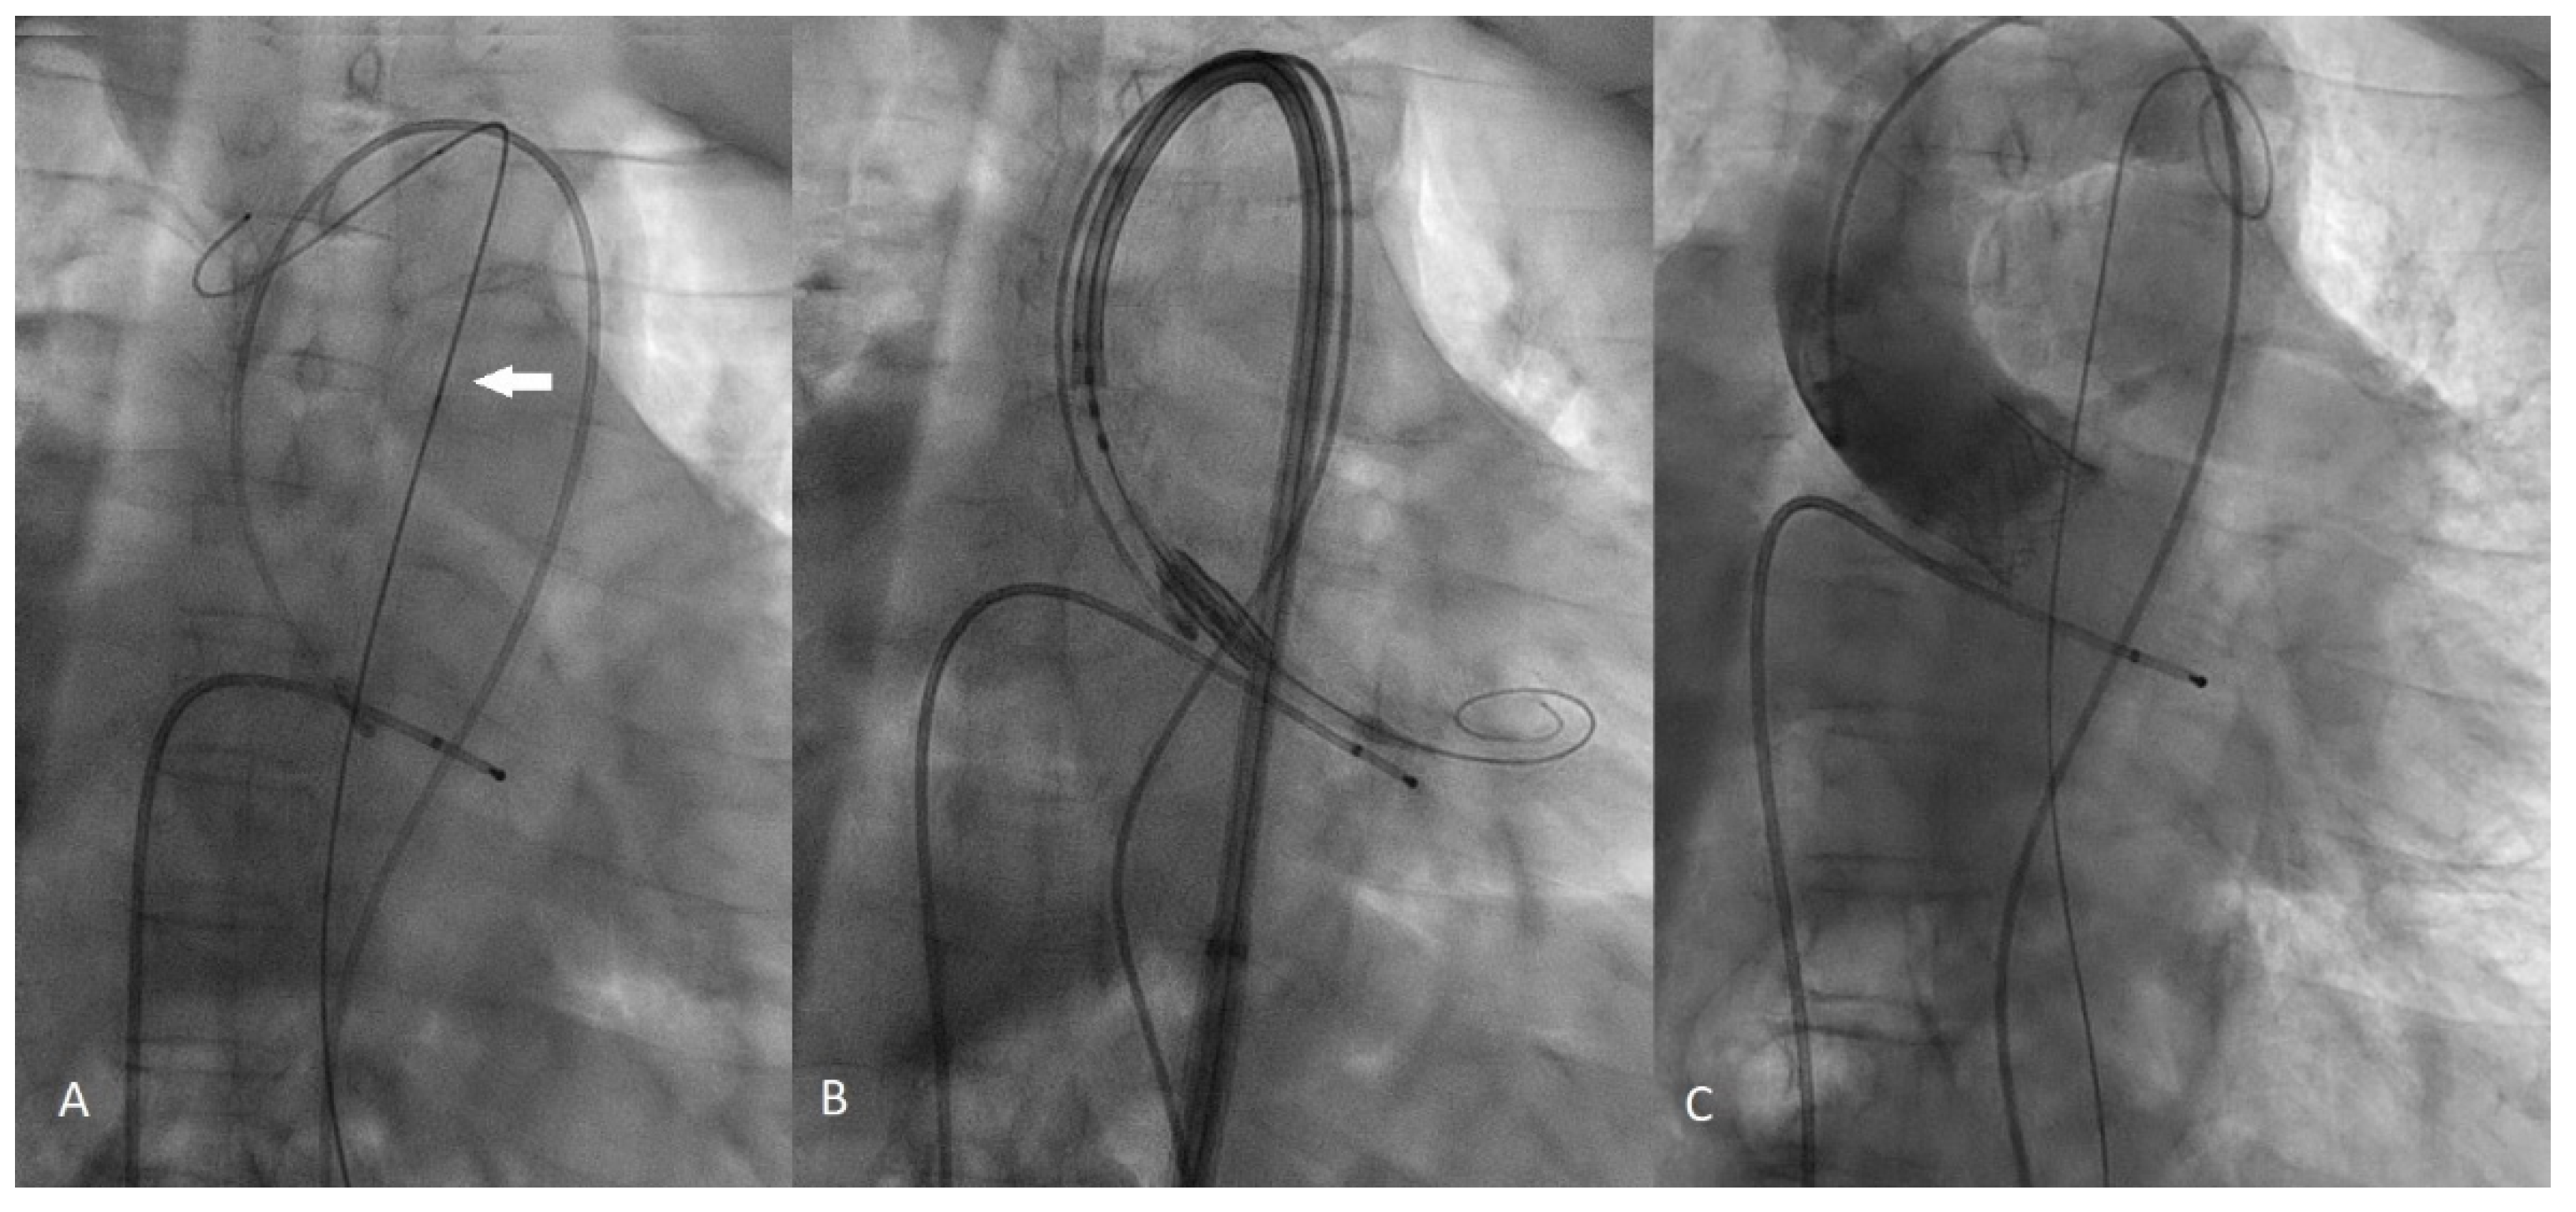

2. Case Presentation